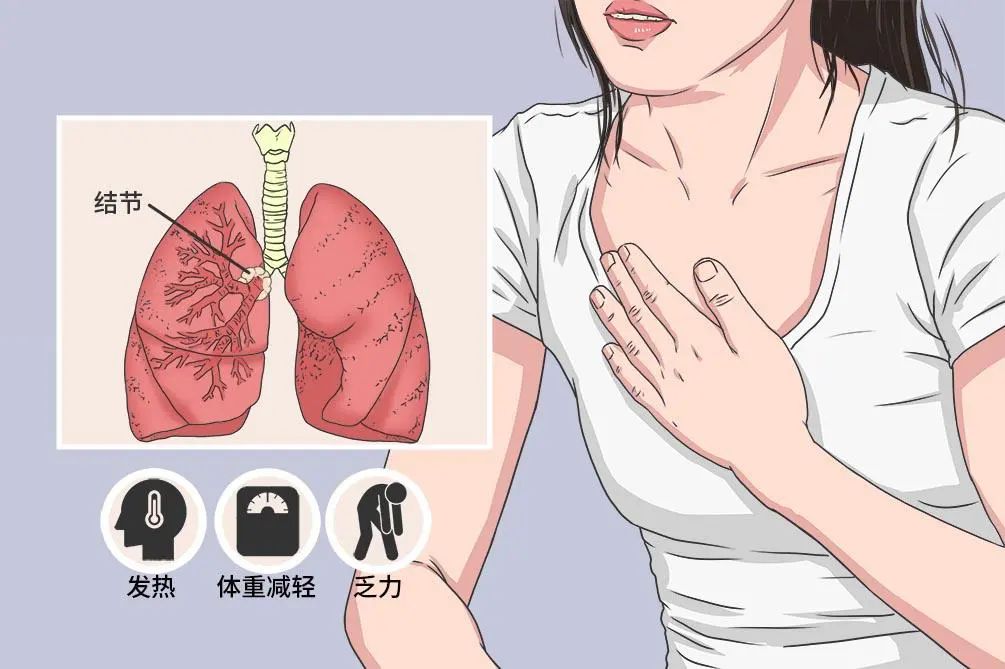

发现肺结节不知所措?一篇文章带你全面了解!

大家好!我是“肺结节”。随着老百姓体检意识的提高以及胸部CT体检的普及发展,“我”越来越频繁地出现在大众视野中,甚至成为很多胸部CT报告的“焦点”。每年体检后,就是“我”刷存在感的热门时候啦!无数人拿着体检报告惶惶恐恐地奔走就医,跑医院、找医生,“医生!我的肺长了个结节,是不是肺癌呀?”“医生,我肺上这个结节要不要动手术切掉?”急匆匆的步伐是内心无比慌乱的映射。为啥?因为他们怕我是“肺癌”呀!

他们的担心也不无道理,确实很多早期的“肺癌”是由“我”发展而来的。同时“我”也是“百变”的:大小不等、形态多样、善恶皆有可能!既然大家都谈“我”色变,那么今天“我”就来个详细的自我介绍,看完这篇文章,下个跟“我”不期而遇的你,就不用忧心忡忡,急病乱投医了!

“我”(肺部结节),是在肺部影像表现为直径≤30mm的局灶性、类圆形、密度增高的实性或者亚实性肺部阴影,可以是孤立性或多发性,不伴肺不张、肺门淋巴结肿大和胸腔积液。按不同性质分类可分为不同类型肺结节:

“我”从哪里来

感染、炎症、肺部原发肿瘤、转移瘤以及其他良性疾病的表现都可能会表现为肺部结节。虽然肺结节百变多样,但也不用过于担心。